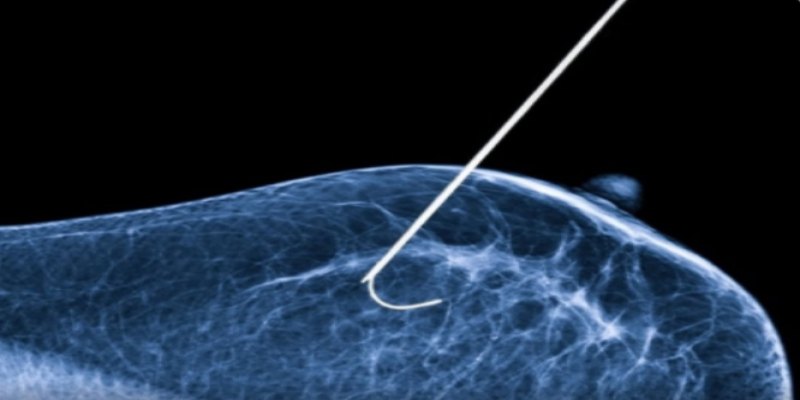

ESPERANÇA: Nova técnica de congelamento com nitrogênio é utilizada contra o câncer de mama